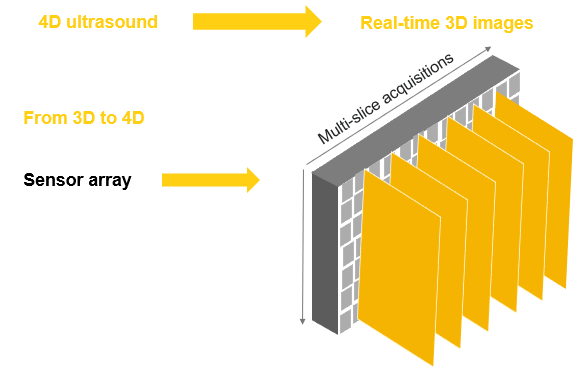

4D Ultrasound

A 3D ultrasound allows the visualization of static 3D images. Whereas a 4D ultrasound allows the addition of a live streaming video, showing the motion of the moving structures, such as the fetal heart, or the blood flow in various vessels. In other words, a 4D ultrasound is actually a 3D ultrasound in live motion. The 4D image is achieved by repeating 3D images in short intervals.

As explained previously, 3D ultrasound is a series of data that contains a large number of 2D planes (B-mode images). Once the volume is acquired using a dedicated 3D probe, you can navigate through the different 2D planes that make up the total volume. Once you have all the data, you can also see the different planes by rotating the volume.

4D

4-dimensional ultrasound imaging is based on acquiring and displaying a series of 3D data with their reconstructions and multi-planar renderings in real-time while scanning the patient. 4D scans show moving 3D images of your baby for example.